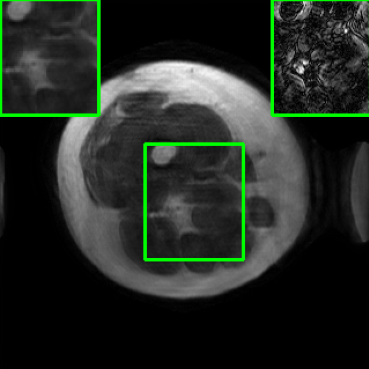

Results for the DIDN-based Reconstructor: To demonstrate adaptability to different network architectures, Table II compares reconstruction performance on the test set with the DIDN denoiser-based MoDL architecture. Average PSNR values with LONDN-MRI are compared to those with networks trained globally at different training set sizes. We ran only iteration of LONDN-MRI, where the reconstruction with a pre-trained (global) network was used to find neighbors. PSNR values for the oracle LONDN-MRI reconstructor are also shown. The overall performances with the DIDN-based architectures are better than with the UNet-based unrolled networks. The PSNRs for LONDN-MRI are consistently and similarly better than for the globally trained network across the different training set sizes considered, indicating potential for LONDN-MRI in improving state-of-the-art models. Fig. 6 visually compares reconstructions and reconstruction errors (in zoomed in region) for different methods. We can see that the LONDN reconstructors capture the original image features more sharply and accurately than the globally learned reconstruction.

| Ground Truth | Global | LONDN-MRI | Oracle |

| (1 iteration) | |||

![]() |

| PSNR = dB | PSNR = 34.15 dB | PSNR = 34.46 dB | PSNR = 34.54 dB |